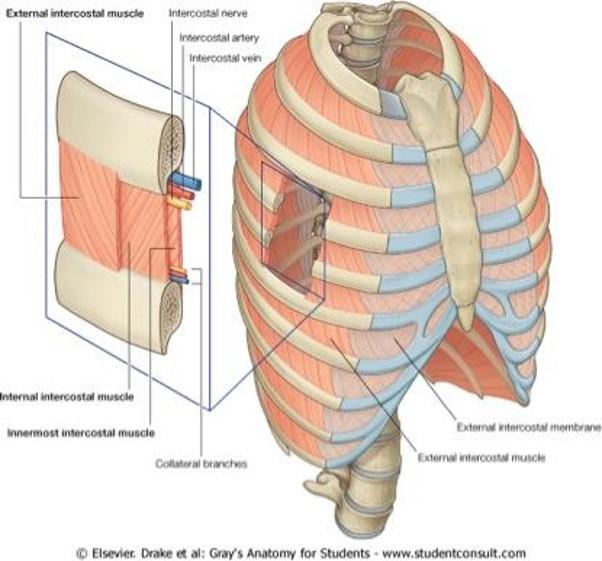

identify the actions of these muscles and their relationship to each other in space?

- External intercostals (E)

- Internal intercostals (I)

- Innermost intercostals (IM)

External intercostals (E)...inspiration...most superficial

Internal intercostals (I)...expiration

Innermost intercostals (IM)...elevate?…not completely understood...most deep

what is between the internal intercostals and the innermost intercostals? which muscle is on top?

when looking at a picture how do you identify these muscles, what should you look for?

BV's and nerves in between them

internal intercostal on top

basically, look for the innermost muscle and if its muscle colored it is the innermost intercostals...if it looks like a layer was peeled and you see nerves traveling horizontal, it indicates that you are looking at the internal intercostals

notice the external intercostal muscles

look at picture